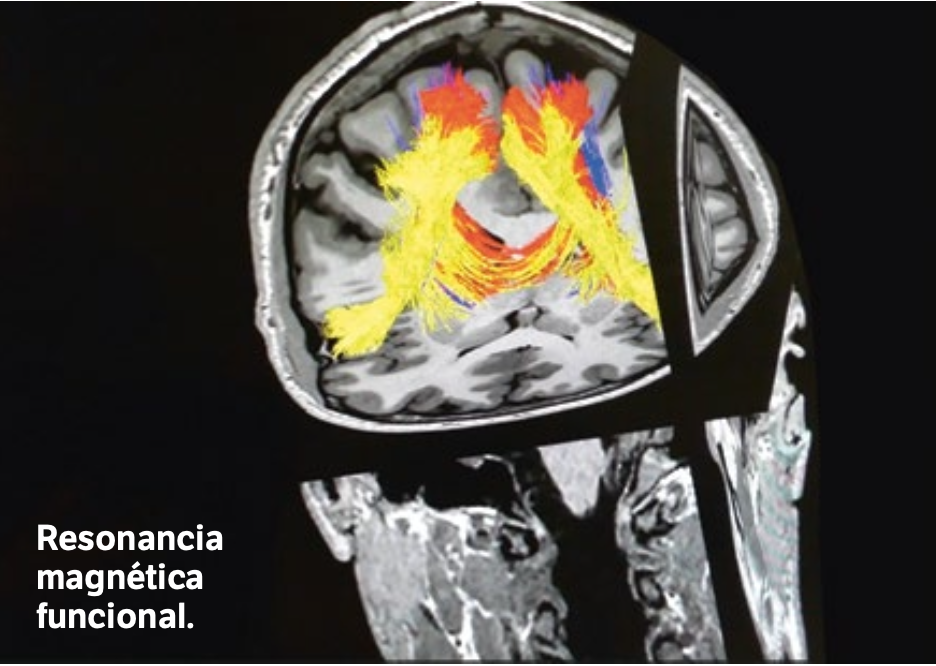

Con el fin de que la intervención no afectara a la parte del cerebro que determina esas emociones, el Hospital Universitario Quirónsalud realizó un mapeado previo de las conexiones cerebrales tanto corticales como subcorticales mediante una resonancia magnética funcional en la que se sometía al paciente a un test de empatía y a pruebas de movilidad de su pierna izquierda para mostrar las zonas de activación del cerebro. «El objetivo era identificar en estudios de imagen avanzados las áreas cerebrales relacionadas con la empatía, y lo conseguimos colocando un visor al paciente dentro de la resonancia magnética donde podía ver imágenes de ojos que expresaban alegría, tristeza, temor», expone Mar Jiménez, jefa asociada del Servicio de Diagnóstico por la Imagen de este centro.

Esta prueba permitió identificar y detectar las zonas concretas de la corteza cerebral relacionadas con las emociones del paciente, para así saber qué áreas se debían respetar lo máximo posible durante la intervención para que no se vieran afectadas. El objetivo final pasa por «conseguir la máxima resecabilidad del tumor con el menos déficit posible para el paciente», sentencia la doctora Jiménez.